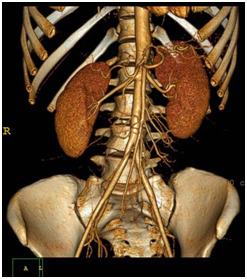

Sempre investindo em tecnologia, a Diagcenter oferece em Vargem Grande do Sul o que há de mais inovador em exames de tomografia: a Tomografia Multislice de 16 canais com Reconstrução Tridimensional (3D). A Tomografia Computadorizada Multislice é um aparelho de última geração que possibilita ao médico radiologista, que laudará seu exame, uma avaliação muito segura e precisa.

Após o exame, profissionais especializados realizam a reconstrução das imagens obtidas. Por vezes, quando seu médico solicita ou ainda quando são identificados dados importantes em seu exame, é realizada a reconstrução tridimensional. Com esta tecnologia, as imagens do exame ficam mais claras e objetivas para melhor interpretação e diagnóstico do médico radiologista.